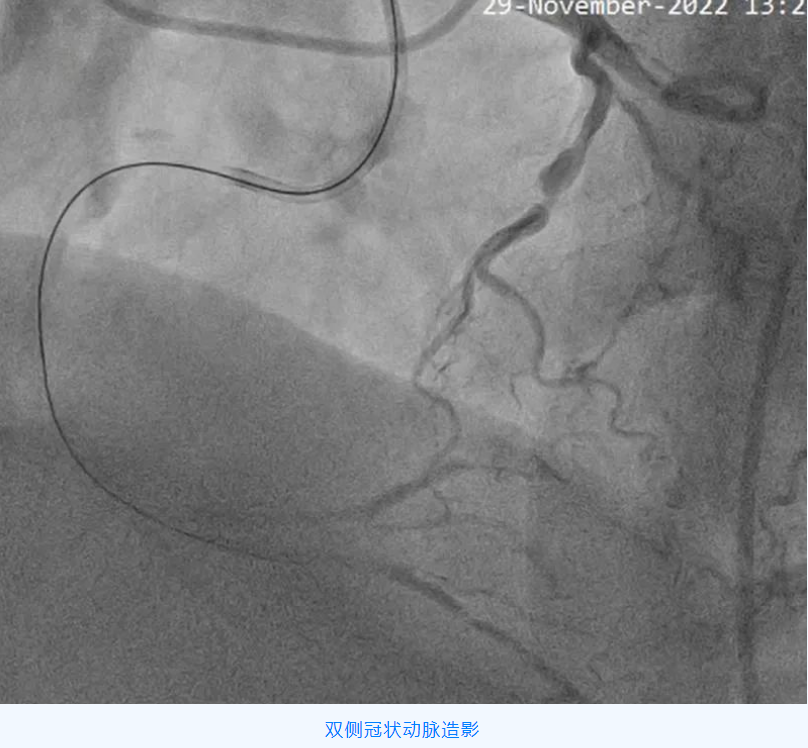

家住阎村的赵爷爷,今年75岁,近一年来反复出现胸痛、胸闷,行冠脉CTA检查发现冠状动脉三支病变,其中一根血管完全闭塞,需进一步行冠脉介入治疗。

冠状动脉慢性完全闭塞病变(CTO),即冠状动脉血管腔完全闭塞,且持续闭塞的时间大于 3 个月的病变。对于病人而言,成功开通 CTO 可以延长生命、改善心脏功能、增加心肌电活动稳定性,减少心律失常事件,而且还可以增加以后可能出现的冠状动脉闭塞事件耐受性及提高生活质量,越是年轻患者,开通 CTO 获益越大。

但该手术难度大、成功率低、并发症、再狭窄、再闭塞发生率高,被公认为是冠状动脉介入治疗的天花板。CTO 病变的开通成功率已成为评价医院心血管内科介入治疗水平高低的一个主要指标。